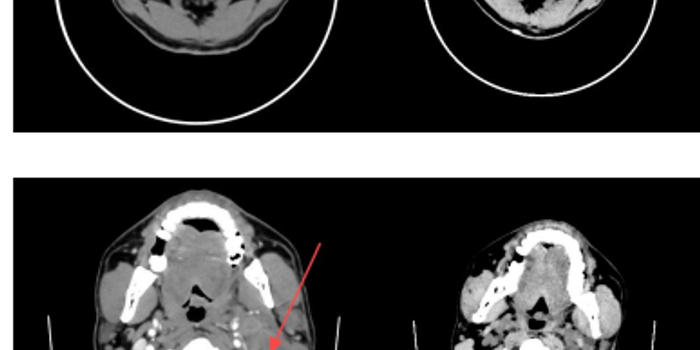

(一)鼻咽癌

治疗前CT显示鼻腔、颈部肿块明显,经调强放射治疗33次后1个月复查,肿块显著缩小,患者病情得到有效控制。